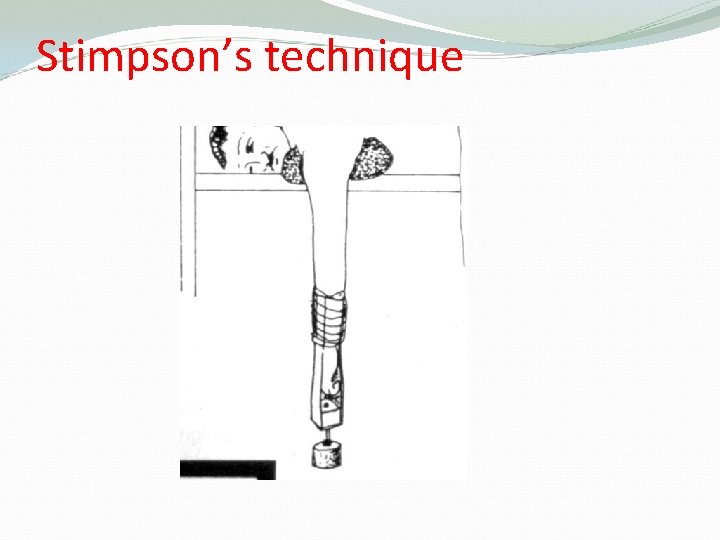

Methods of Reduction of anterior shoulder Dislocation Hippocrates Method ( A form of anesthesia or pain abolishing is required ) Stimpson’s technique ( some sedation and analgesia are used but No anesthesia is required ) Kocher’s technique is the method used in hospitals under general anesthesia and muscle relaxation

Stimpson’s technique